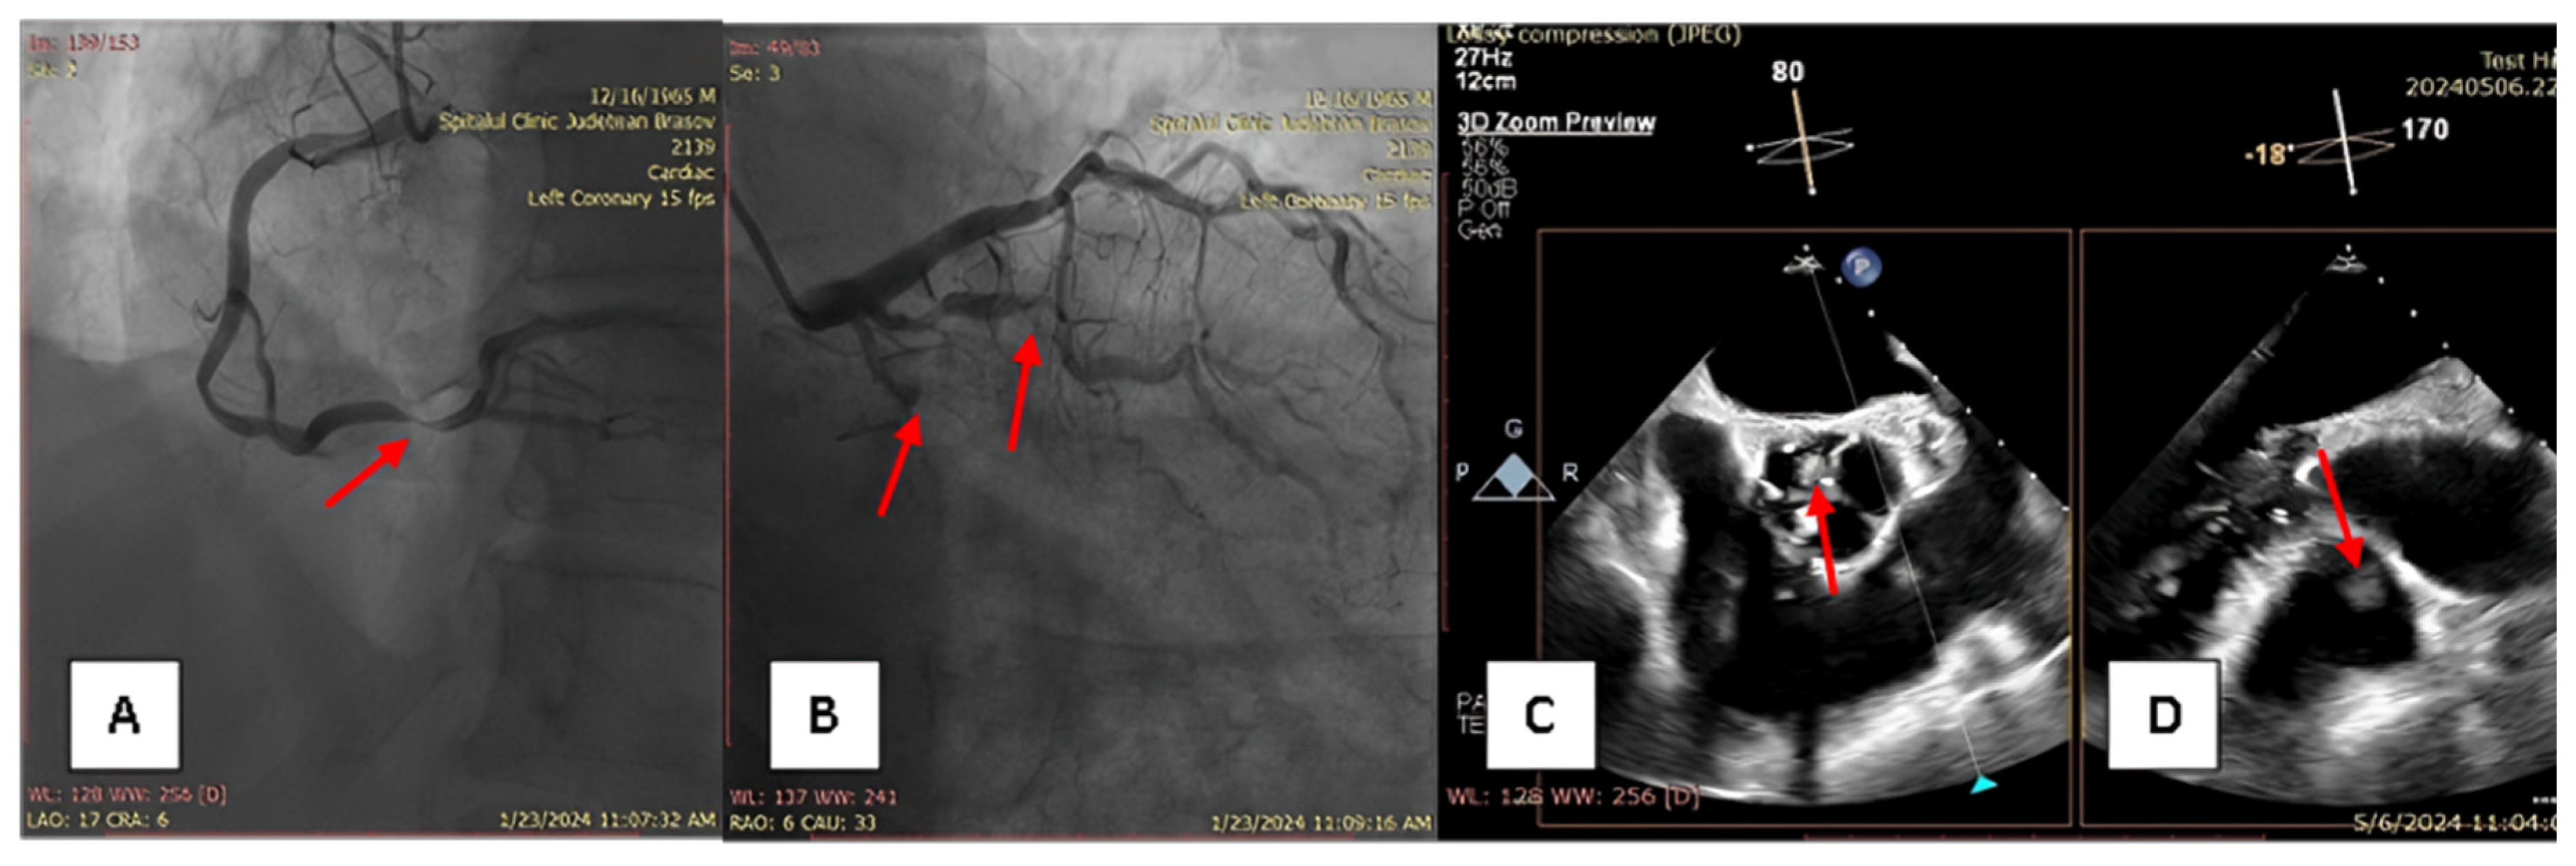

A 58-year-old male patient with multiple cardiovascular risk factors (high blood pressure, dyslipidemia, peripheral arterial disease, smoker) and a relevant family history (father had a myocardial infarction at age 56) with a history of pituitary adenoma surgery presented with persistent exertional dyspnea. TTE revealed a round, oval tumor attached to the pulmonary valve. The ejection fraction was estimated visually at 55%, with no segmental or global kinetic abnormalities and no signs of pulmonary thromboembolism (PE). The dyspnea persisted; therefore, the patient underwent coronary angiography, which revealed chronic occlusion of the circumflex artery, severe distal stenosis of the right coronary artery, and severe stenosis of the intermediate branch (Figure 1A,B). To accurately assess the tumor formation, the patient underwent cardiac MRI, which described a tumor formation (1.1 × 0.8 cm) as iso-/hypointense on T1-weighted sequences, mildly hyperintense on T2-weighted sequences, with no central enhancement but peripheral enhancement with gadolinium on delayed post-contrast sequences. These tissue characteristics supported the diagnosis of a papillary fibroelastoma (Figure 2A,B). Additionally, no other cardiac tumor structures were identified, and no signs of acute or chronic pulmonary embolism were detected. After obtaining the patient’s written consent and following discussions within the Heart Team, the patient underwent excision of the tumor formation from the pulmonary valve and coronary artery bypass grafting. Intraoperative transesophageal echocardiography (TEE) revealed a round, oval, mobile, well-defined tumor approximately 1.1 × 0.8 cm in diameter, attached to the surface of the right cusp of the pulmonary valve (Figure 1C,D). The tumor did not exert a hemodynamic impact on the valve, was not associated with pulmonary stenosis, and was accompanied by only mild pulmonary regurgitation. No other significant valvular pathologies were observed, and there was no echocardiographic evidence of PE. The surgical intervention was performed via sternotomy, under cardiopulmonary bypass with central cannulation: arterial in the ascending aorta and venous in the right atrium. Cardiac arrest was achieved using Calafiore cardioplegia. Initially, the distal coronary anastomoses were completed, followed by a longitudinal incision of approximately 4 cm in the pulmonary trunk to access the tumor. The tumor was friable, mobile, measuring approximately 1.1 × 1.0 cm, and attached to the pulmonary artery side of the right cusp of the pulmonary valve (Figure 3A). It was completely resected along with a small portion of the right pulmonary cusp that included its implantation base. Since only a small amount of valvular tissue was resected, valve repair was successfully performed using a continuous suture with 5.0 Prolene, Ethicon Inc., Cornelia, GE, USA, without the need for autologous pericardium or other biological materials (Figure 3B–D). Subsequently, the proximal coronary anastomoses were completed. No residual pulmonary regurgitation was detected. No other tumor formations were detected intraoperatively. The macroscopic appearance of the tumor was similar to a sea anemone when placed in serum (Figure 4A). The diagnosis of papillary fibroelastoma was confirmed by histopathological analysis (Figure 4B,C). The postoperative course was favorable and without complications, and the patient was discharged without further complaints of dyspnea.

Figure 1. (A)—severe stenosis of right coronary artery; (B)—chronic occlusion of circumflex artery and severe stenosis of intermedius branch; (C,D)—transesophageal echocardiography, showing papillary fibroelastoma attached to the right cusp of the pulmonary valve.